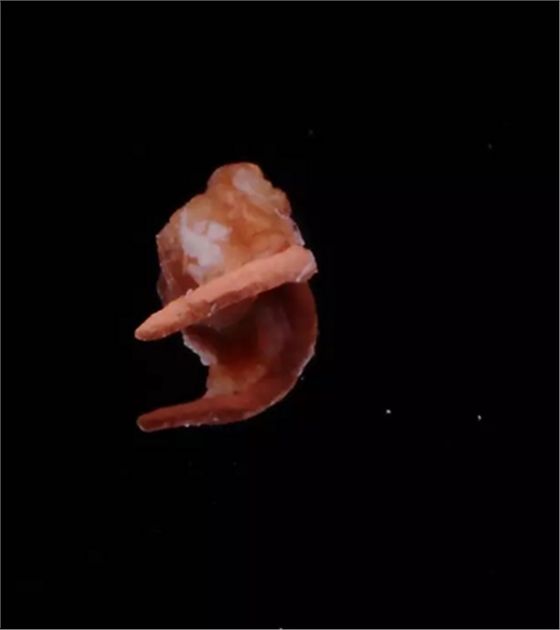

側(cè)穿超出的牙膠尖